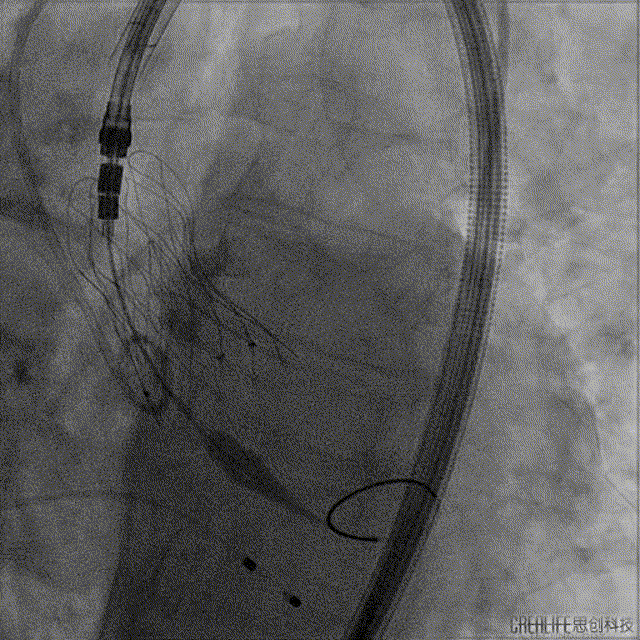

手术过程:

释放过程中:Video 3

完全释放:Video 4